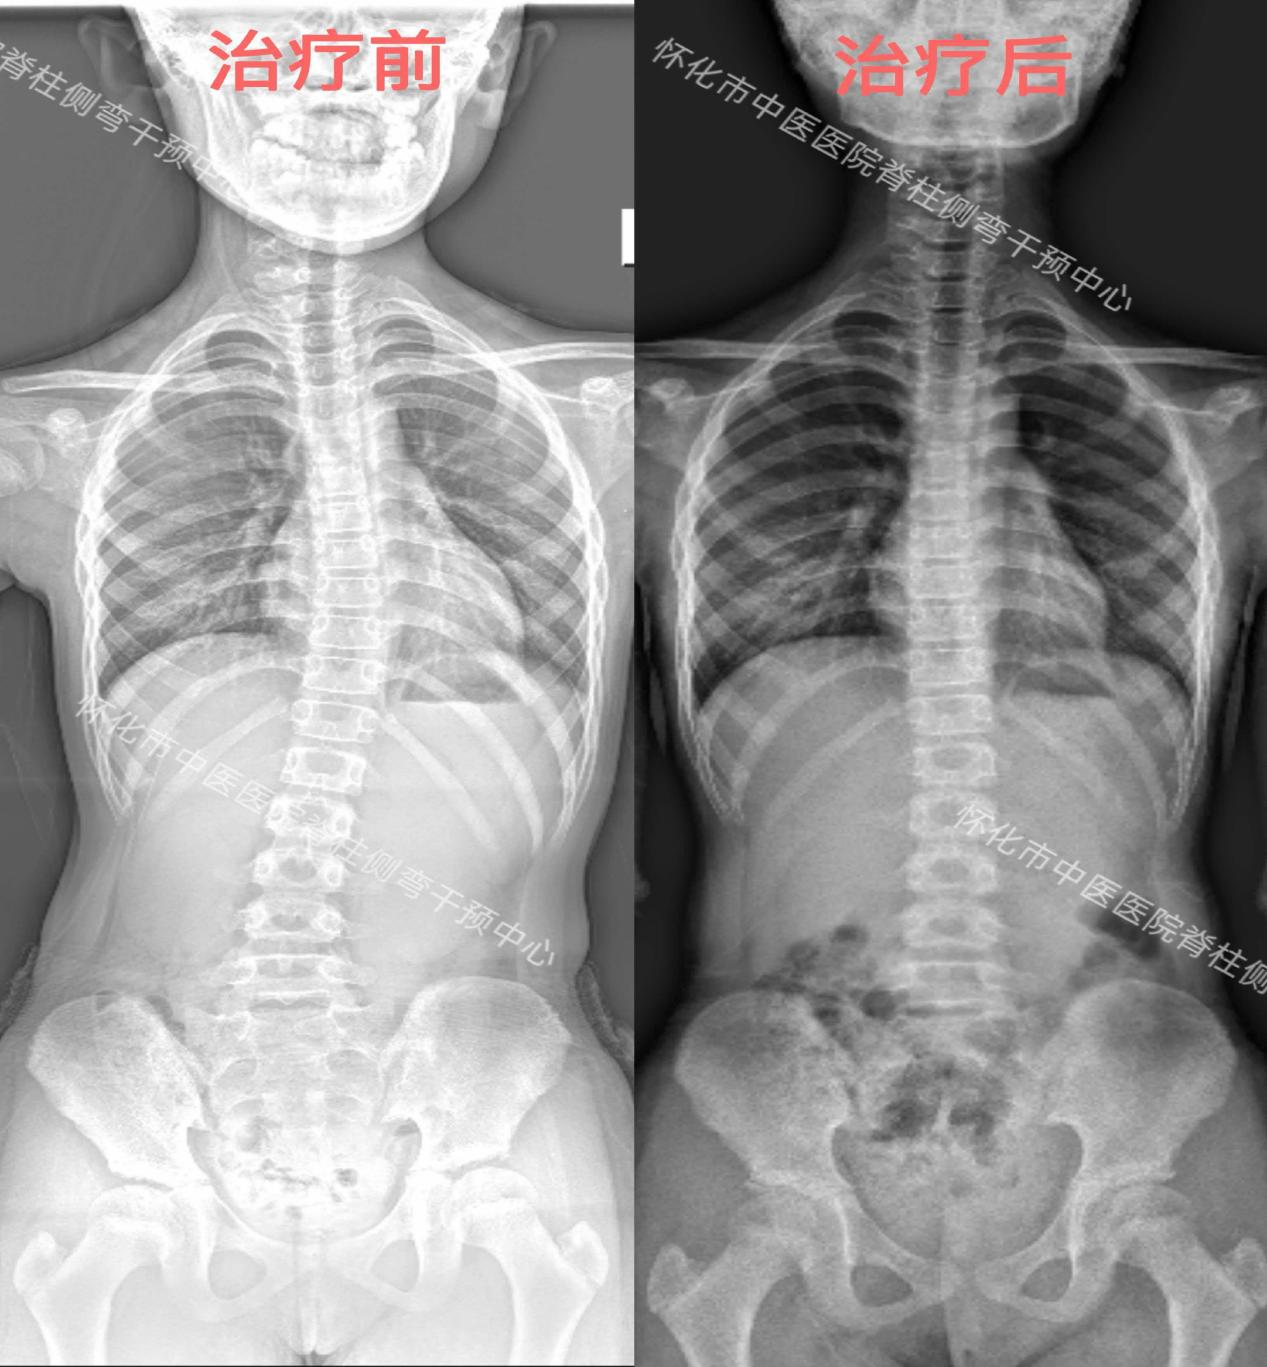

从来没有一蹴而就的康复奇迹,所有向好的转变,都藏在日复一日的坚持里。10岁女孩小刘在怀化市中医医院脊柱侧弯中医药干预中心的帮助下,用数月的持续努力,重拾了挺拔身姿。

2025年3月,小刘同学确诊脊柱侧弯,家人忧心忡忡之际,9月来到怀化市中医医院脊柱侧弯干预中心寻求专业帮助,在接受连续一周的集中规范治疗后,正式开启了为期5个月的间断康复训练。

从确诊时的担忧不安,到训练中的咬牙坚持,再到复查时的惊喜结果,女孩的脊柱侧弯已实现基本矫正。这份成果,是孩子强忍疲惫认真完成每一组动作的坚守,是家长悉心陪伴、全力配合的支持,更是医护人员专业指导、全程护航的责任,三方同心聚力,终让康复希望最终落地。